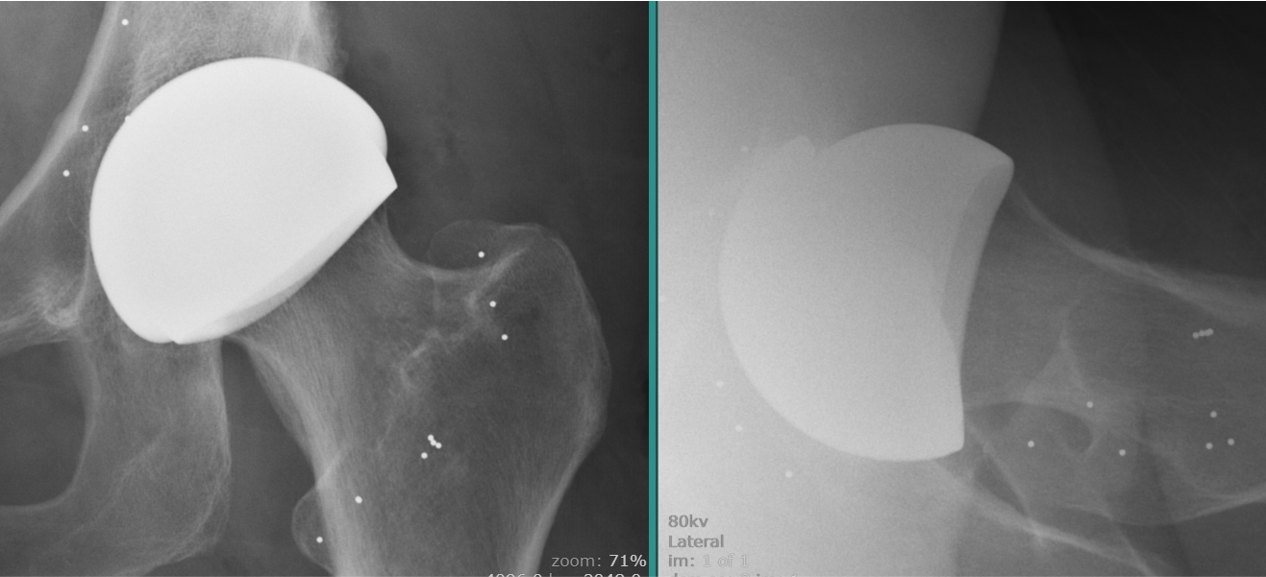

X-rays taken postoperatively show the position and orientation achieved (figures 4a and 4b).